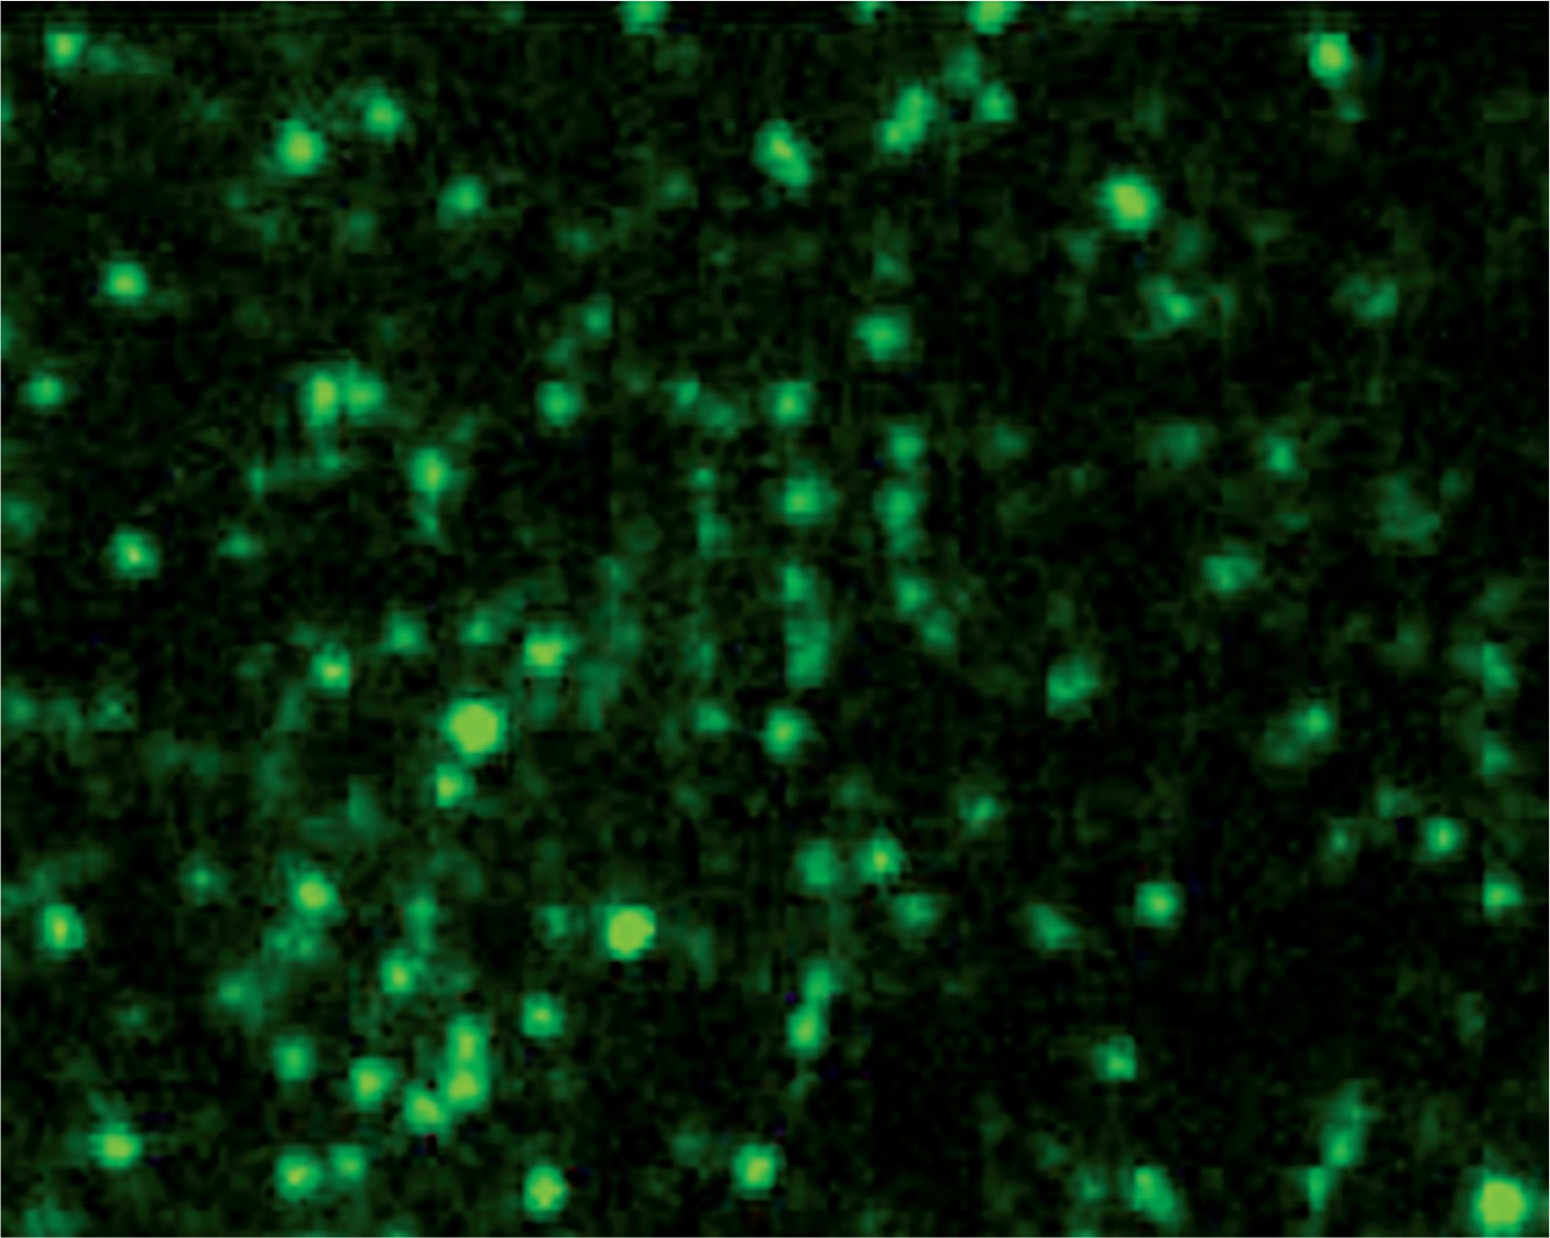

Characterization of the recombinant strain by immunofluorescence microscopy

The spores of the recombinant and wild-type strains were incubated with VP1 polyclonal antibody and FITC-conjugated goat anti-mouse IgG. Fluorescence microscopy showed that the recombinant strain exhibited green fluorescence (Fig. 6), while the wild-type strain did not exhibit green fluorescence (Fig. 6). These results indicated that VP1 was displayed on the surface of spores and had strong immunogenicity.